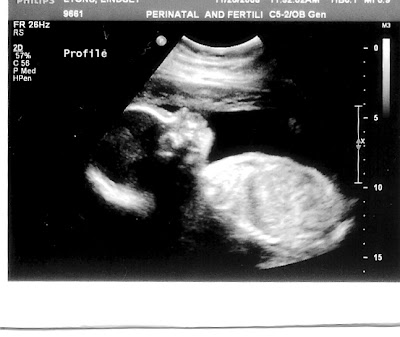

Today Nate and I met with the specialist (high risk pregnancy doctor). We didn't learn much, but we did get to have an ultrasound. It was our 7th ultrasound (most people get between 2 and 3). The little one seemed quite big at 1 lb 12 oz (the doctor said that's normal). He was very sleepy and kept yawning. We also decided he definitely has mom's nose. We can't wait to meet him!

Here is a new picture of the little guy.